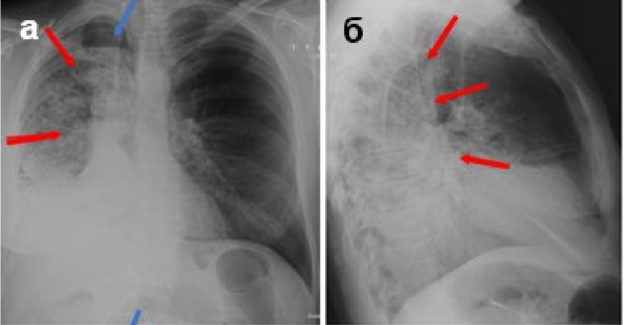

На этом рисунке представлено состояние после торакотомии справа с расширенной нижней билобэктомией с бронхомиопластикой.

Воспалительные изменения правого лёгкого, пневмоторакс справа.

а – цифровая рентгенограмма ОГК в прямой проекции; б – цифровая рентгенограмма ОГК в правой боковой проекции; в – ТС ОГК.

Оставленная верхняя доля правого лёгкого расправлена не полностью, уменьшена в объёме. Прозрачность оставленной доли снижена за счёт гиповентиляции и наличия на этом фоне неоднородного уплотнения лёгочной паренхимы, вероятно воспалительные изменения (красные стрелки), пневмоторакс (синяя стрелка). При ТС – отмечаются участки неоднородного уплотнения лёгочной паренхимы (красные стрелки), на этом фоне прослеживаются просветы бронхов (жёлтые стрелки).